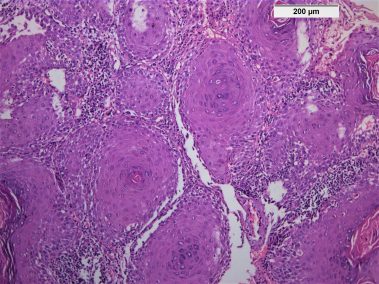

85 years old male came to the clinic suffering from painful ulcer in the left buccal mucosa related to the lower first and second molars. The patient stated that this ulcer appeared three months ago and was preceded by long standing reddish white lesion. The related molars have grade 3 mobility upon clinical examination.